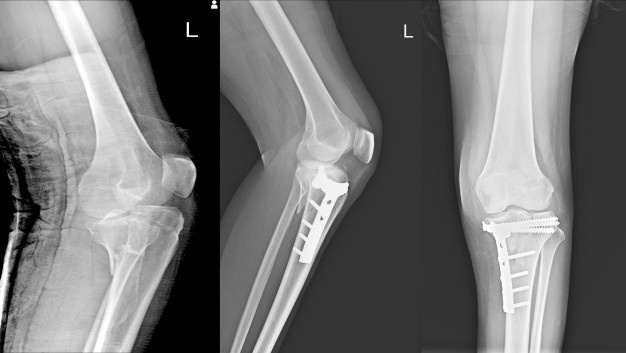

Dokter akan melakukan pemeriksaan fisik guna menguji mobilitas sendi lutut dan melihat apakah ada pembengkakan, memar, kulit lunak maupun rasa hangat di area lutut. Terkadang, pemeriksaan radiologis pun diperlukan guna menegakkan diagnosis. Metode pengobatan nyeri lutut nantinya akan menyesuaikan dengan kondisi nyeri yang Anda alami.